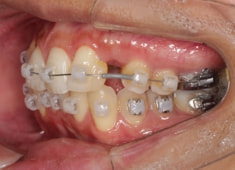

左上3番埋伏歯

治療法:フルパッシブブラケット:T21

治療開始時